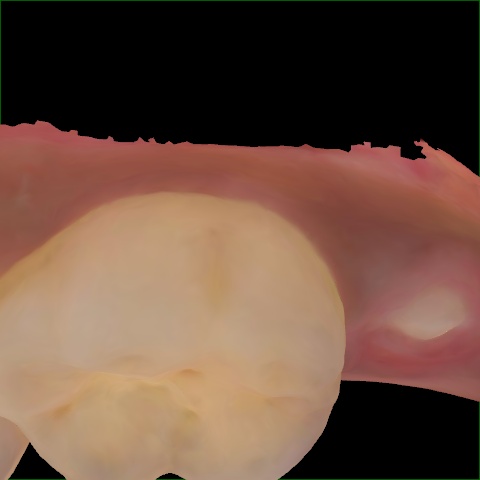

Annotated as "Good"